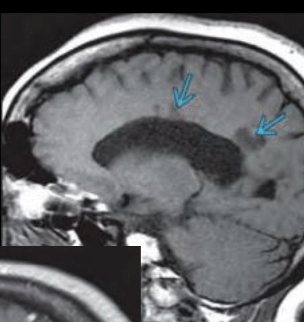

T1 GD

Captación: aguda: activa

Q

ACTIVA capta